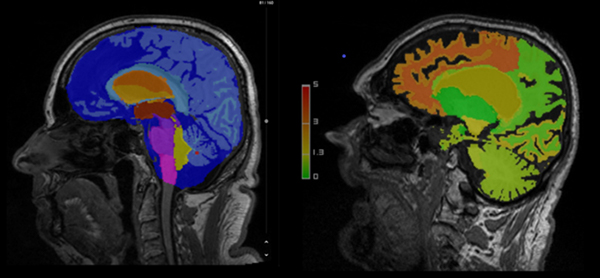

1. 「AI-Rad Companion Brain MR」

頭部MR画像から脳の各部位を自動的にセグメンテーションし,部位ごとにノーマルデータベースと比較することにより,異常のリスクを解析結果画像と定量レポートとして提供する。放射線科医および診療医にこれらの結果をアルツハイマー型認知症やパーキンソン病等のリスク評価に活用することを想定している。

この「AI-Rad Companion Brain MR」について,埼玉医科大学総合医療センター 放射線科 教授 土屋 一洋 氏は以下のように述べている。「この脳形態計測は,主要な構造物を自動的に同定して体積を評価し,正常データベースとの比較で客観的な結果を得ることができます。変性疾患や脱髄疾患での脳の萎縮性変化の評価において有用性が大きいと感じています」*4

AI-Rad Companion Brain MRの臨床画像